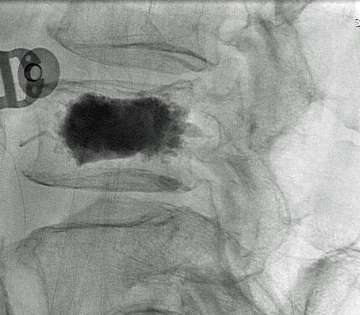

During the procedure, the patient is lightly sedated and lies on their tummy. Under x-ray guidance, we place the needle into the vertebral body (Figure 2). Unlike most pain services where a relatively simple portable C-arm X-ray machine is used, we use the state-of-the-art biplane neuro-angiosuite, which is capable of 3-D navigation in the brain and spine (Figure 3). In rare occasions, placement of the needle is challenging due to previous implantation of metal hardware that obscures the normal bony landmarks, or due to severe osteoporosis. The 3-D navigation capability provides us with the ability to very accurately place the needle without relying on the classic radiological bony landmarks (Figure 4).

Once the needles are placed into the fractured vertebral body, cement is injected through the needles so that it can be stabilized from its inside (vertebroplasty).

If there is a need to restore the height of the fractured vertebral body, a balloon is inflated within the fractured vertebral body prior to cement injection (kyphoplasty / Figure 5). Once the bone cement hardens, it becomes an internal cast and completely stabilizes the lesion (Figure 6).